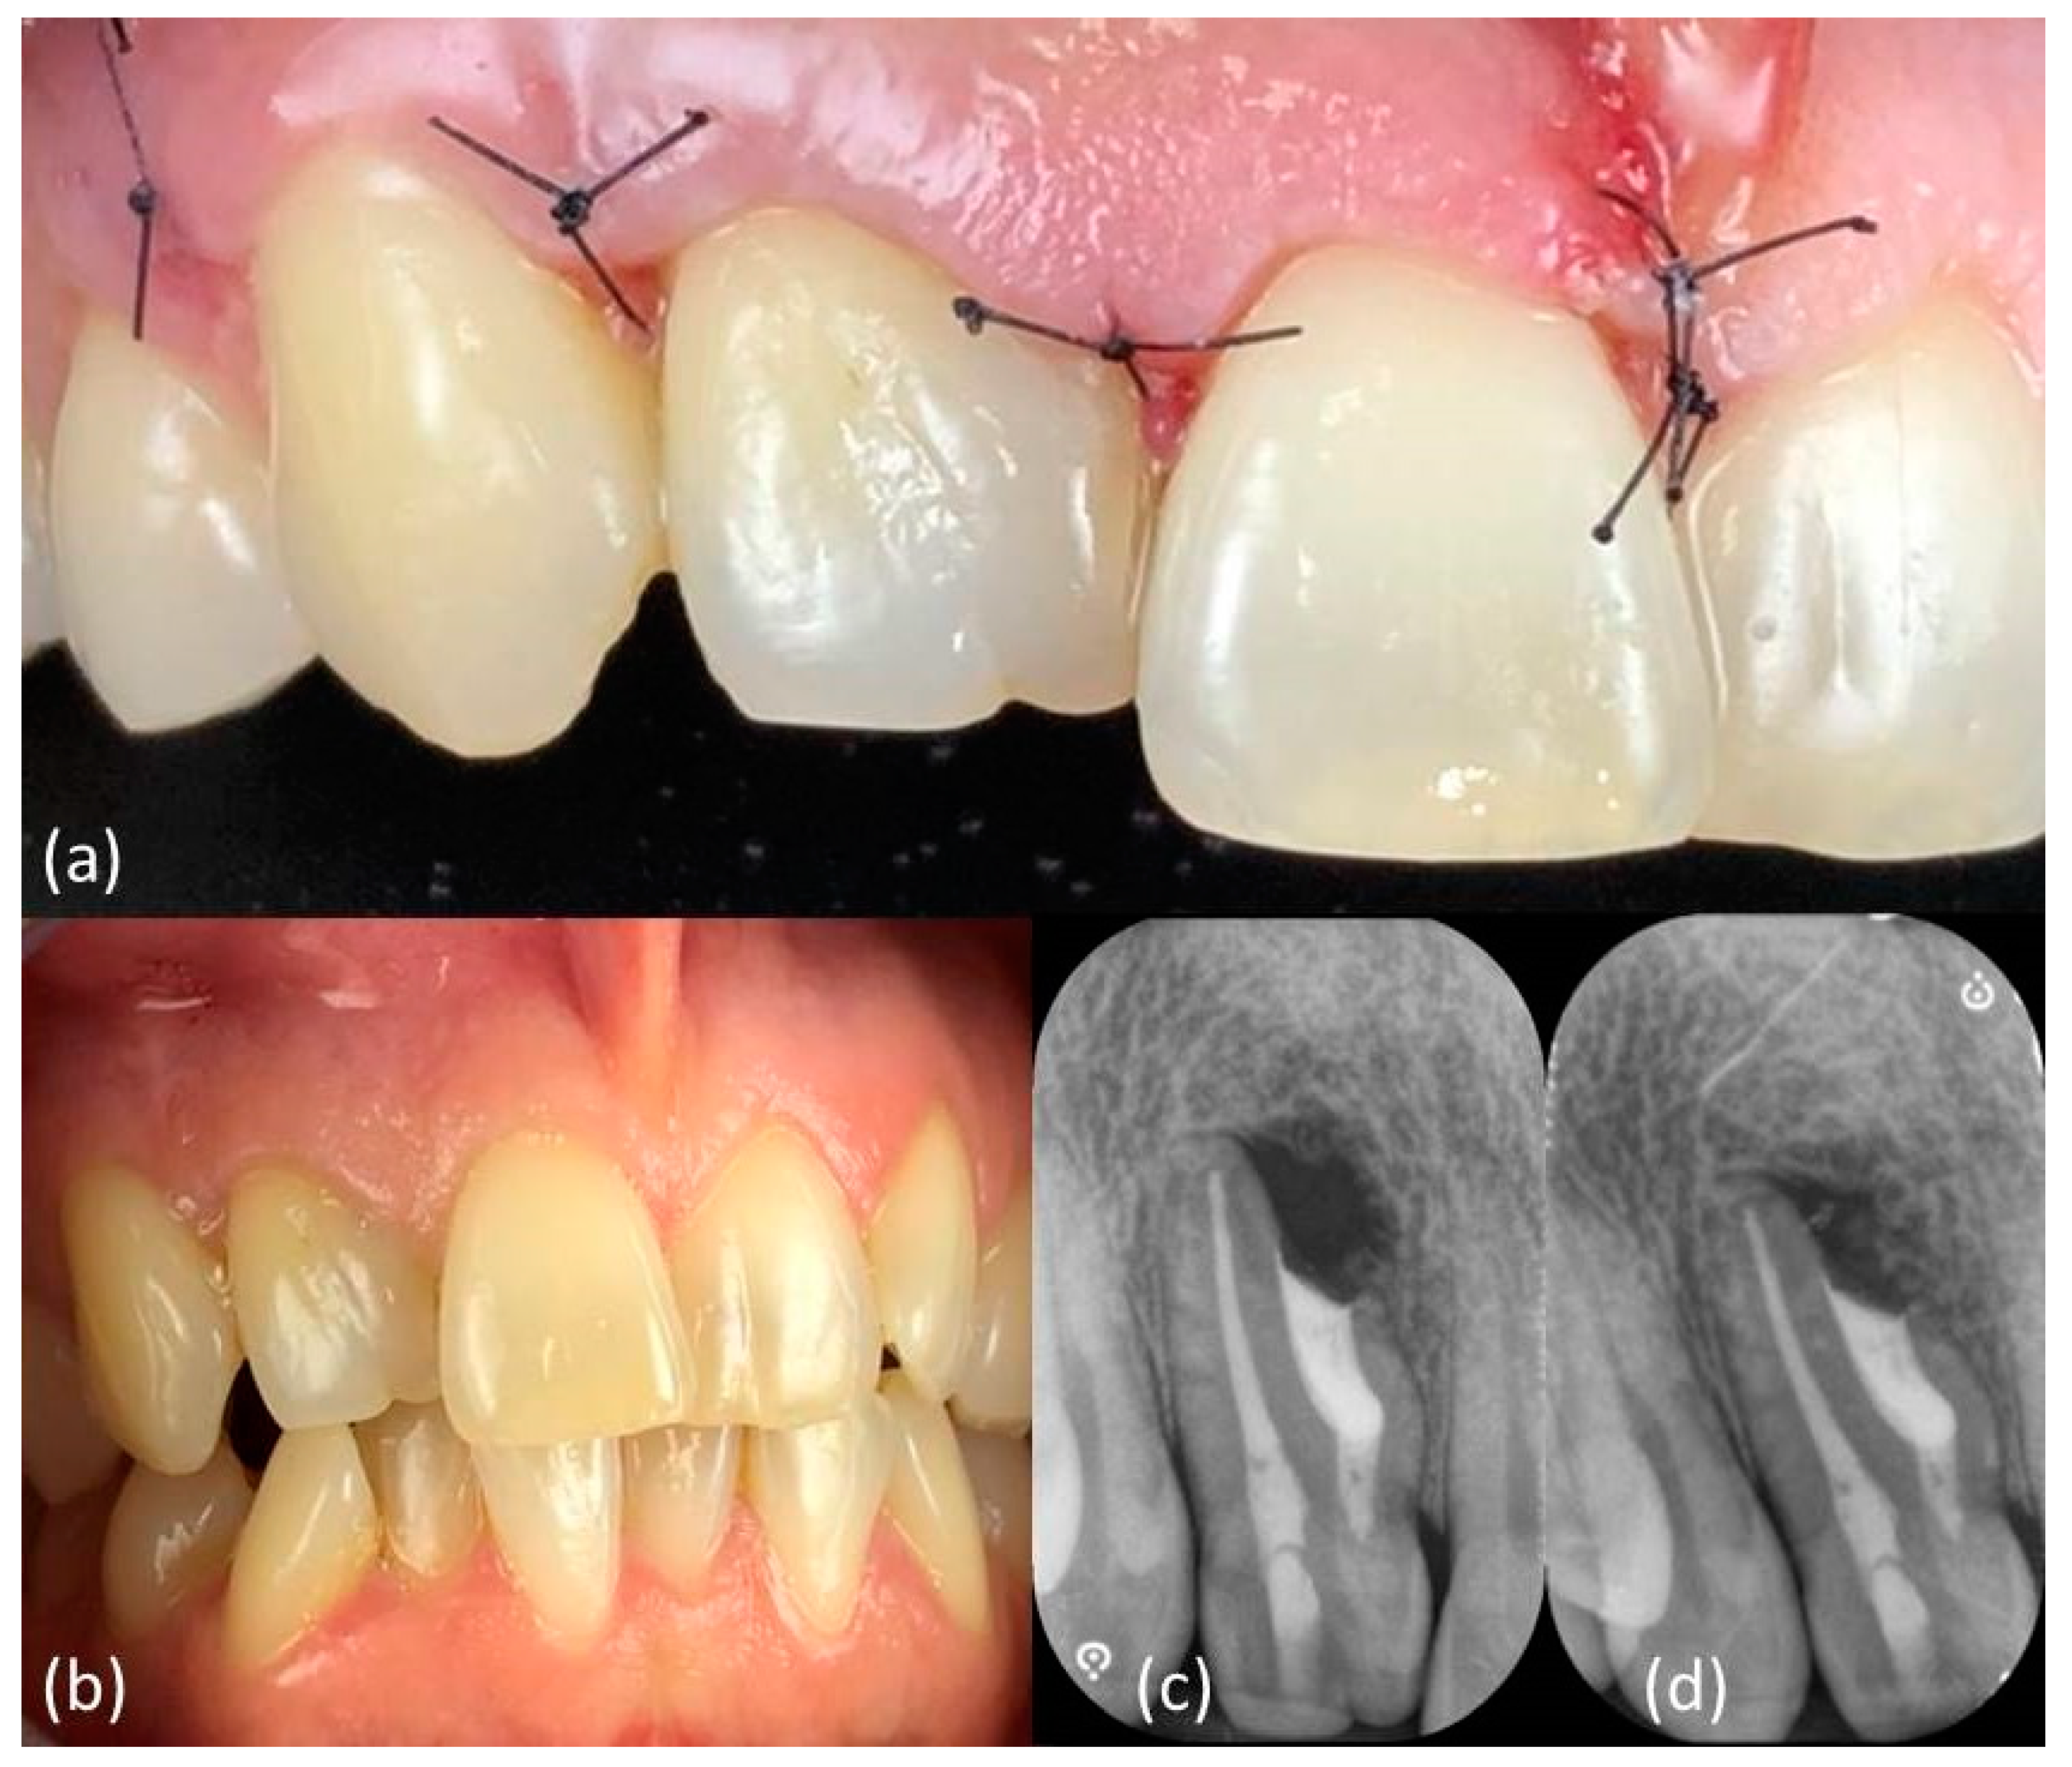

One week later, no discomfort has been reported and primary tissue healing had been achieved, allowing sutures removal (Figure 5a). Clinical (Figure 5b) and radiographic follow-up (Figure 5c,d) showed a positive outcome, with soft tissue and bone healing progression.

Figure 5.

Tissue healing after (a) one week and (b) six months and (c) six-months and (d) twelve-months radiographic follow-up.